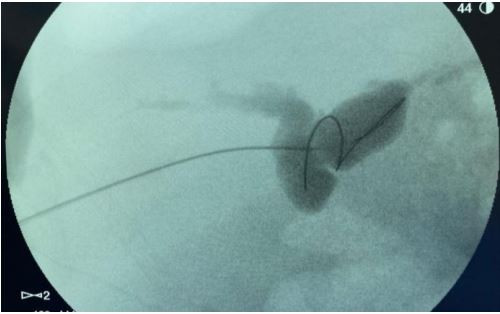

Realizada Colangiopancreatografia Retrógrada Endoscópica (CPRE) com achado abaixo, onde se observa dificuldade de passagem de fio guia devido tortuosidade de colédoco do receptor: